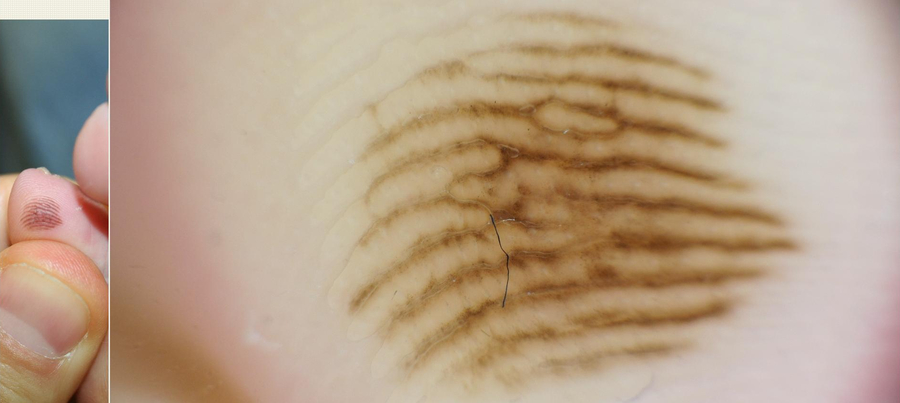

diagnosi computer, lesione pigmentata, nevuscreen Diagnosi computer assistita di una lesione pigmentata cutanea con il Software Nevuscreen.

Diagnosi computer assistita di una lesione pigmentata cutanea con il Software Nevuscreen.

Il videodermatoscopio digitale riporta su un monitor l'iimagine clinica e dermatoscopica dei nei. La qualità dell'immagine è elevatissima, ciò consente una corretta esecuzione della tecnica. Il computer equipaggiato con un particolare software di gestione dati, permette di creare per ogni paziente una cartella personalizzata in cui si raccolgono tutti i dati anamnestici ed una mappa di lesioni neviche che devono essere sottoposte a controllo periodico. Di ogni neo viene memorizzata l'immagine clinica e dermatoscopica che così sarà facilmente confrontabile con altre immagini della stessa lesione presenti in database, in modo da poter apprezzare ogni eventuale minimo cambiamento.

Il software presente presso tutti gli Skin Center (Nevuscreen) è in grado di poter eseguire in maniera automatica l'ABCD di tutte le lesioni e fare una previsione diagnostica, di poter avere immediatamente la misurazione geometrica di ogni neo (Area, Perimetro, Diametro massimo e minimo) in maniera oggettiva e riproducibile (www.nevuscreen.it).